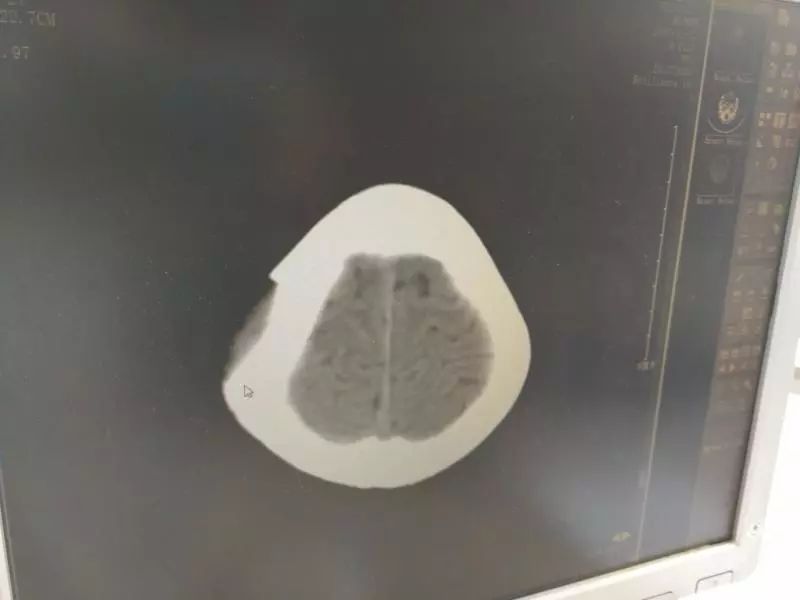

头颅CT显示,浩浩头骨被砸出一个乒乓球大小的坑,深度超过1厘米,伤处的脑组织也受到挤压陷了进去,“颅内高压,需要立即手术!”接诊的小儿神经外科主任医师石坚说,浩浩受伤的是顶部运动区,不立即手术的话,相应脑功能或出现不可逆损害,继发偏瘫、癫痫就麻烦了。

拍片显示,浩浩头部被砸出一个坑,脑组织也受到了压迫。